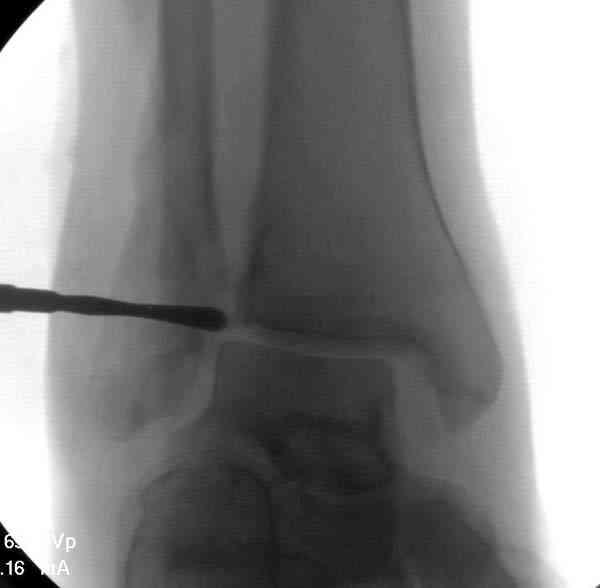

Здесь представлено решение похожей проблемы. Больной в течение года лечился консервативными мерами, и боли в голеностопе были основным показанием к операции.

Проведена обычная стандартная процедура по исправлению неудовлетворительного состояния голеностопного сустава, где кроме удлинения малоберцовой с применением compression tension device за проксимальный конец пластины, проведено замещение трикортикальным графтом из крыла, освобождение синдесмоза и медиальной щели от

фибротических масс с фиксацией.

Дополнительно у больного плоская стопа, во время операции провели небольшую скользящую остеотомию, надеемся, что поможет.